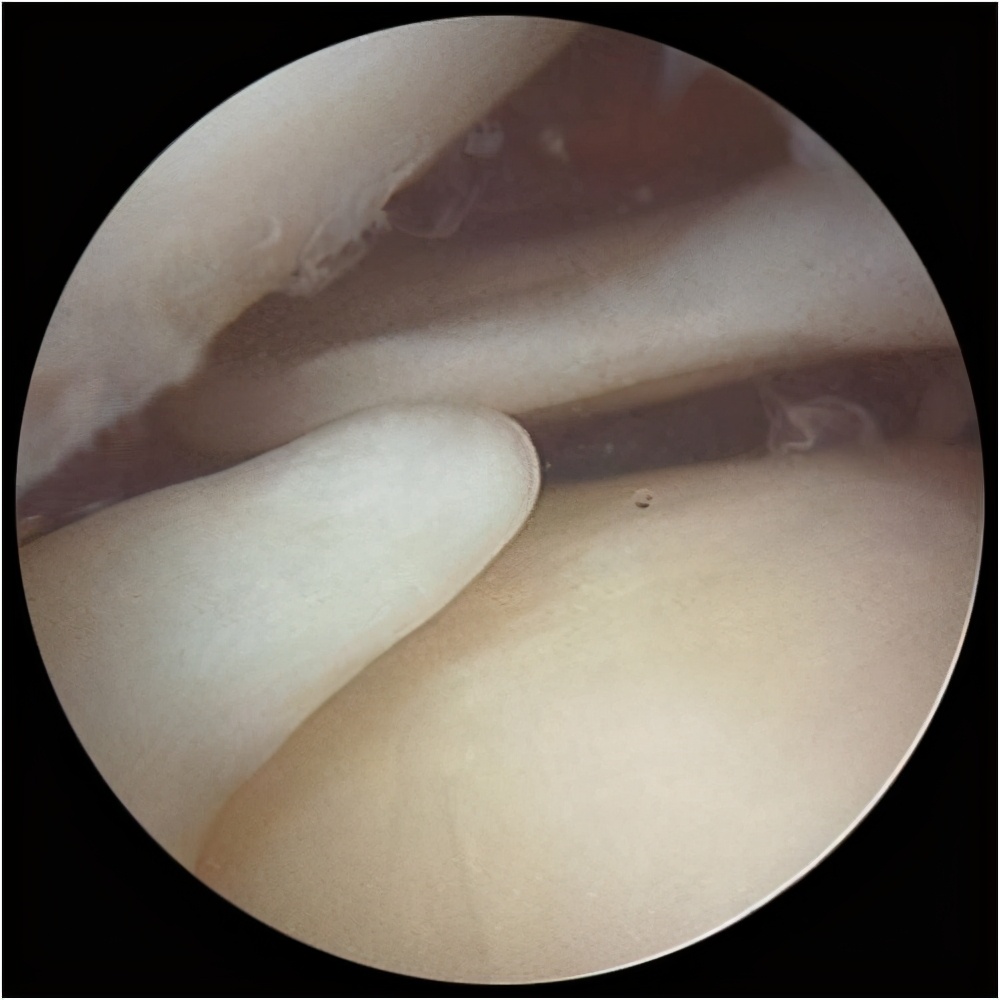

手术治疗:若半月板损伤严重,有固定的位置的剧烈疼痛,伴关节交锁、活动受限等症状时应尽早于医院就诊。医师将根据患者的病史、症状、体征、MRI检查结果做出临床诊断,如果需要手术的话,医生会根据关节镜下半月板损伤的具体情况,考虑具体的手术方式:关节镜下半月板缝合、半月板部分切除、半月板次全切或者半月板切除等。

关节镜下半月板